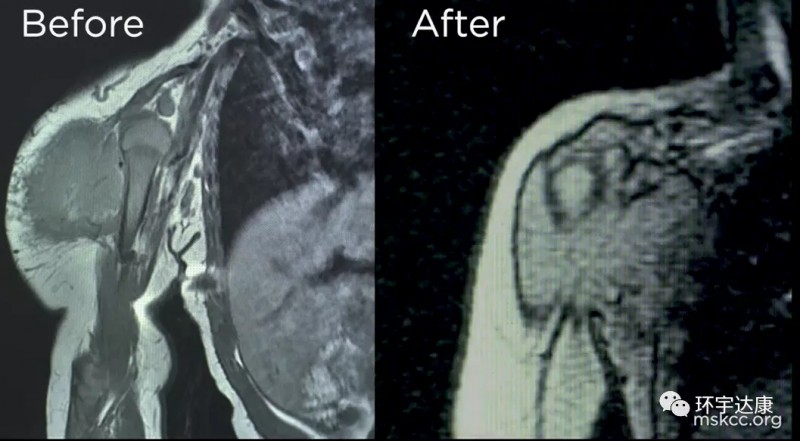

但是另Anna夫妇震惊的是,三天后,蕾哈娜(Rihanna)的巨大肿瘤就以肉眼可见的速度迅速缩小,他们带着蕾哈娜(Rihanna)来到医院,医生们也惊呆了!他们从未见过药物起效的速度如此之快。肿瘤已经长了几个月了,然而,一周内就快速消退了!

五个月后,外科医生来会诊后,高兴的告诉他们,如果肿瘤没有缩小,手术会影响蕾哈娜(Rihanna)的手臂功能,甚至需要截肢,导致她无法正常生活,但是现在肿瘤已经缩小了,可以通过手术将肿瘤完全切除,并且不会影响她日后的生活。

手术非常顺利,蕾哈娜(Rihanna)剩余的所有肿瘤都被切除,并且胳膊的功能没有收到任何影响。现在她已经快4岁了,医生说她已经完全没有肿瘤的迹象。